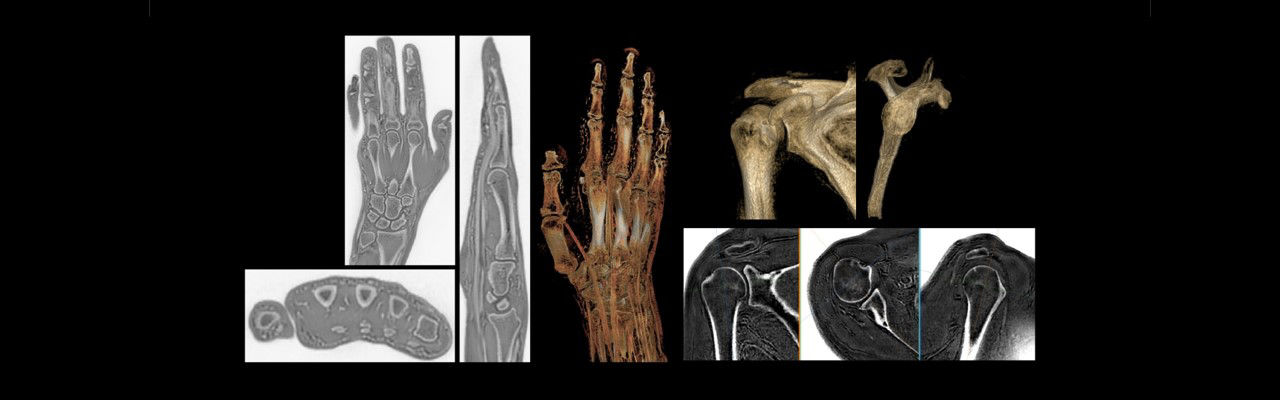

Magnetic Resonance Imaging (MRI) is a highly effective imaging modality, traditionally utilized for the visualization of soft tissues. Other tissues such as ligaments, tendons, calcifications, and cortical bone structures are not traditionally visible using MRI, but are typically assessed from the signal void within the image. Innovative MRI technology from GE Healthcare has now made it possible to capture these structures using novel pulse sequences such as zero echo time (ZTE).

This new development in MR bone imaging provides a computed tomography (CT)-like image contrast in 3D isotropic resolution without any ionizing radiation to the patient. It is an attractive alternative for those patients, such as young children or pregnant patients where a CT exam would pose a dose concern.

Specialty clinicians such as orthopedists were quick to realize the potential clinical applications for bone imaging with MRI for musculoskeletal (MSK) conditions. It is currently being utilized to obtain morphological information about the cortical bone structure in anatomies such as the shoulder, hip, skull, foot/ankle and spine. Its potential is especially welcome when longitudinal CTs are required, and particularly when low-dose CTs are unavailable. Having both soft tissue assessment and bone imaging within the same exam can also reduce the burden on the patient to attend two separate imaging modality appointments and may also lead to reduced healthcare costs.

In MRI, bone is typically visualized with a void signal when using conventional clinical pulse sequences with echo times (TEs) of a several milliseconds or longer. The lack of direct signal originating from cortical bone impairs the ability of conventional MRI sequences to provide utility for assessing bone,2 but using ZTE technology, it is now possible to image cortical bone surfaces. ZTE enables the acquisition of signal from tissues exhibiting the shortest T2 values.3 ZTE imaging also has greater signal-to-noise ratio and scan-time efficiencies that are conducive to acquiring images at near-isotropic resolution and multiplanar reconstruction. The post-processing of ZTE images provides contrast between soft tissue and bone comparable to that at CT.4

Adding a 3 to 4 -minute ZTE sequence to an MRI acquisition does not interrupt the clinical workflow and provides clinicians with a one-stop shop for assessing soft tissue contrast in musculoskeletal (MSK) imaging and providing complementary cortical bone information that can be co-registered with the soft tissue series. The MRI bone imaging acquisition can be used across the patient’s entire anatomy.

“We’ve incorporated ZTE into most of our protocols,” Dr. Aydingoz explains. “We also rely on it for critical shoulder angle measurement, for osseous bankart lesions, and for glenoid stock estimation and glenoid track assessment. We find the ZTE image is very much like the CT image and often, there’s no need to take an additional CT.”